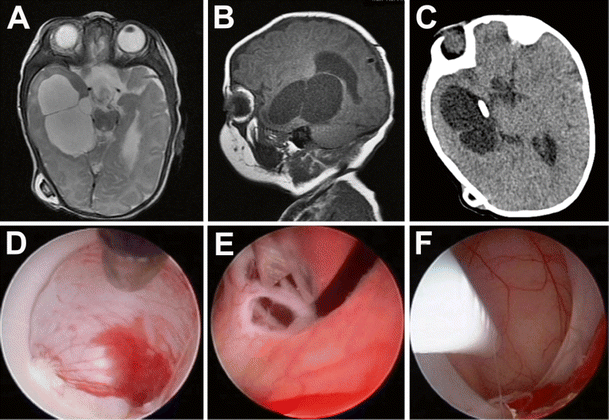

Five-year-old with a radiologically enlarging left ventricular cyst presenting with headache. Preoperative T2-weighted axial (a) and sagittal (b) MR imaging demonstrate a 5-cm intraventricular cyst. A left occipital endoscopic approach was chosen for the endoscopic cyst fenestration (c) with care made to reach both the occipital and frontal pole of the cyst to restore normal CSF pathways within the lateral ventricle (f). Postoperative MRI demonstrates decompression of the left lateral ventricle (d, e)

Four-year-old with a complex history of hydrocephalus and multiloculated ventricles (a, b). Endoscopic fenestrations of multiple intraventricular compartments was performed (d, e) followed by endoscopy-assisted shunt placement (c, f) into the right temporal horn